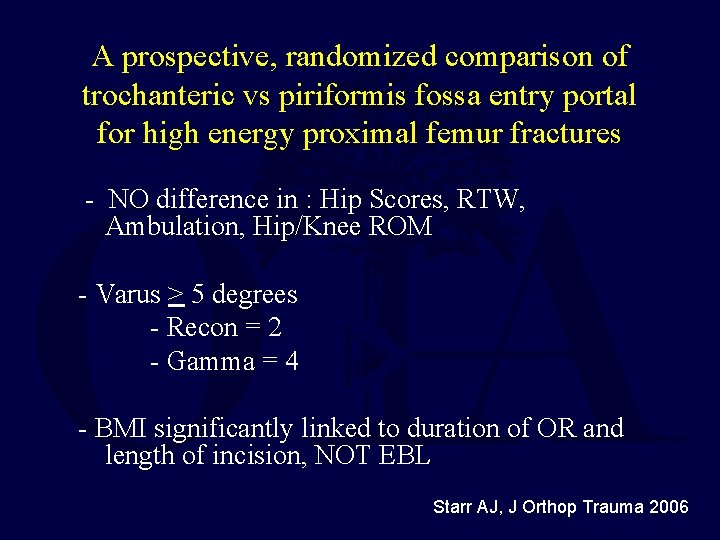

A prospective, randomized comparison of trochanteric vs piriformis fossa entry portal for high energy proximal femur fractures - NO difference in : Hip Scores, RTW, Ambulation, Hip/Knee ROM - Varus > 5 degrees - Recon = 2 - Gamma = 4 - BMI significantly linked to duration of OR and length of incision, NOT EBL Starr AJ, J Orthop Trauma 2006